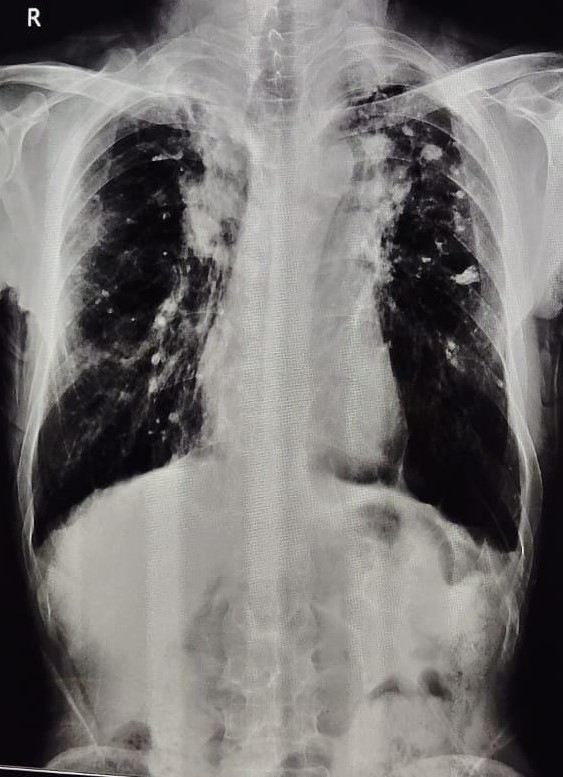

| 197 | IGGMC, Nagpur, Nagpur | P2 | 29-4275 | Meerabai Kuril | Consent taken on Paper | 58 Yrs. |

Provisional Diag : Post TB Bronchiectasis?

Final Diag : Post TB Sequeale (CxR- Bilateral Fibro cavitary Changer) |

Post TB Sequelae | CxR- Bilateral Fibro cavitary Changer | Abnormality visible on x-ray |